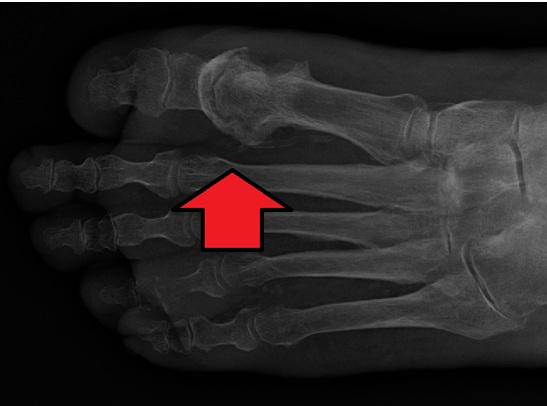

Osteomyelitis is een infectie van het bot of het beenmerg. Bacteriën zijn meestal de oorzaak. Door deze ziekte kunnen stukken botweefsel afsterven en losraken. Daardoor kunnen dan weer abcessen ontstaan. Een diabetische voetinfectie kan tot osteomyelitis leiden. Dokters moeten dit dan zo vroeg mogelijk vaststellen. Zo’n diagnose vindt vaak plaats op grond van de bezinkingssnelheid van erytrocyten (rode bloedcellen).